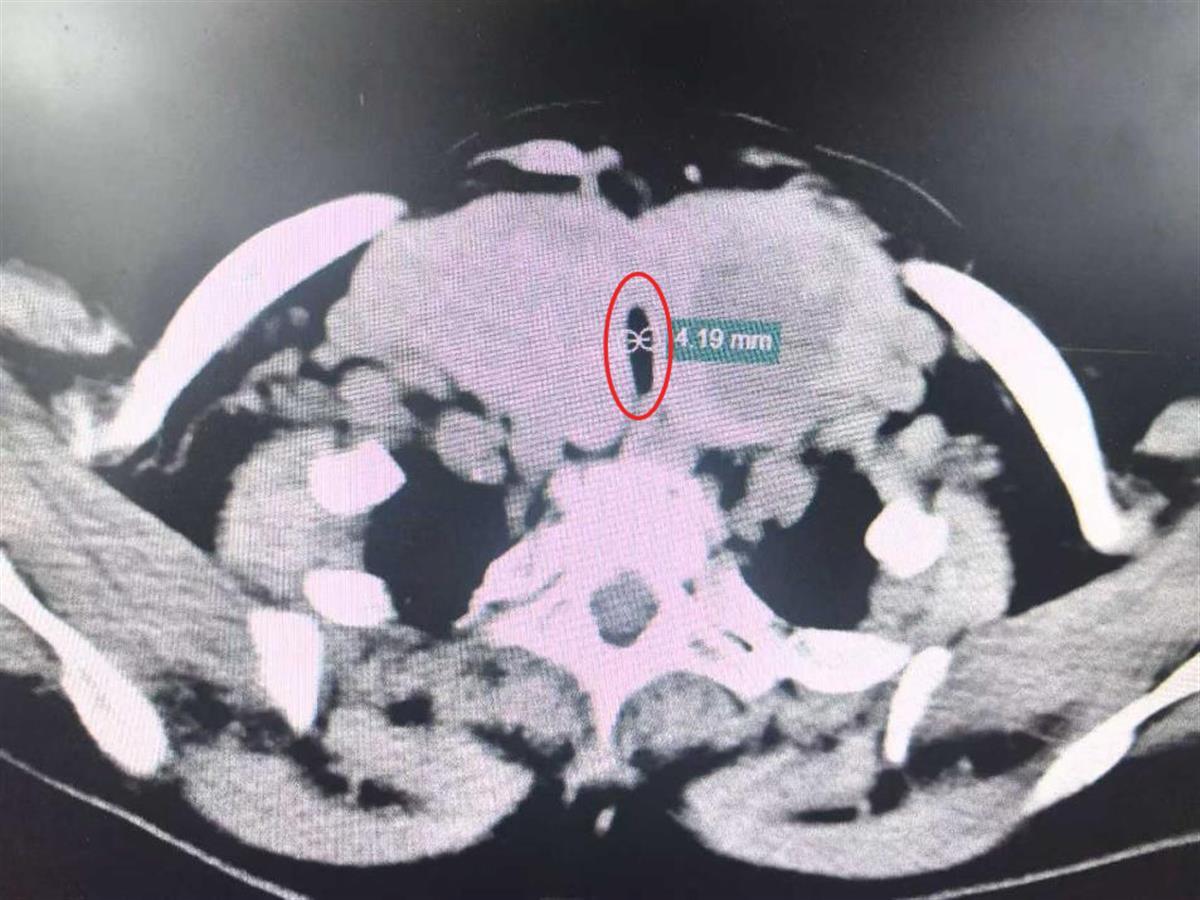

武汉大学人民医院乳腺甲状腺外科主任姚峰教授接诊后,通过颈部CT检查发现,婆婆的病情的确十分棘手。

双侧巨大甲状腺压迫气管,导致气管仅剩“一线天”,最窄处仅4.1毫米

导致婆婆呼吸困难的原因是一处巨大胸骨后甲状腺肿,肿块最大直径超过了10厘米。双侧巨大甲状腺压迫着气管,导致气管仅剩“一线天”,最窄处仅4.1毫米。更要命的是,肿块顺着胸廓入口向胸腔蔓延,最低处紧邻主动脉弓,就像一颗“不定时炸弹”悬在胸腔内;而颈段甲状腺肿块则向两边横向发展,压迫着颈动脉鞘。如果任由肿块继续生长或者有任何轻微的痰液堵塞,都可能让婆婆瞬间窒息。